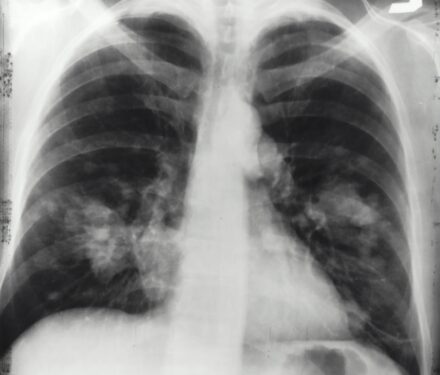

Lung cancer is the leading cause of cancer death worldwide, and is frequently associated with cachexia. Cachexia is a devastating syndrome of weight and muscle wasting, affecting as many as 80 per cent of advanced cancer patients.